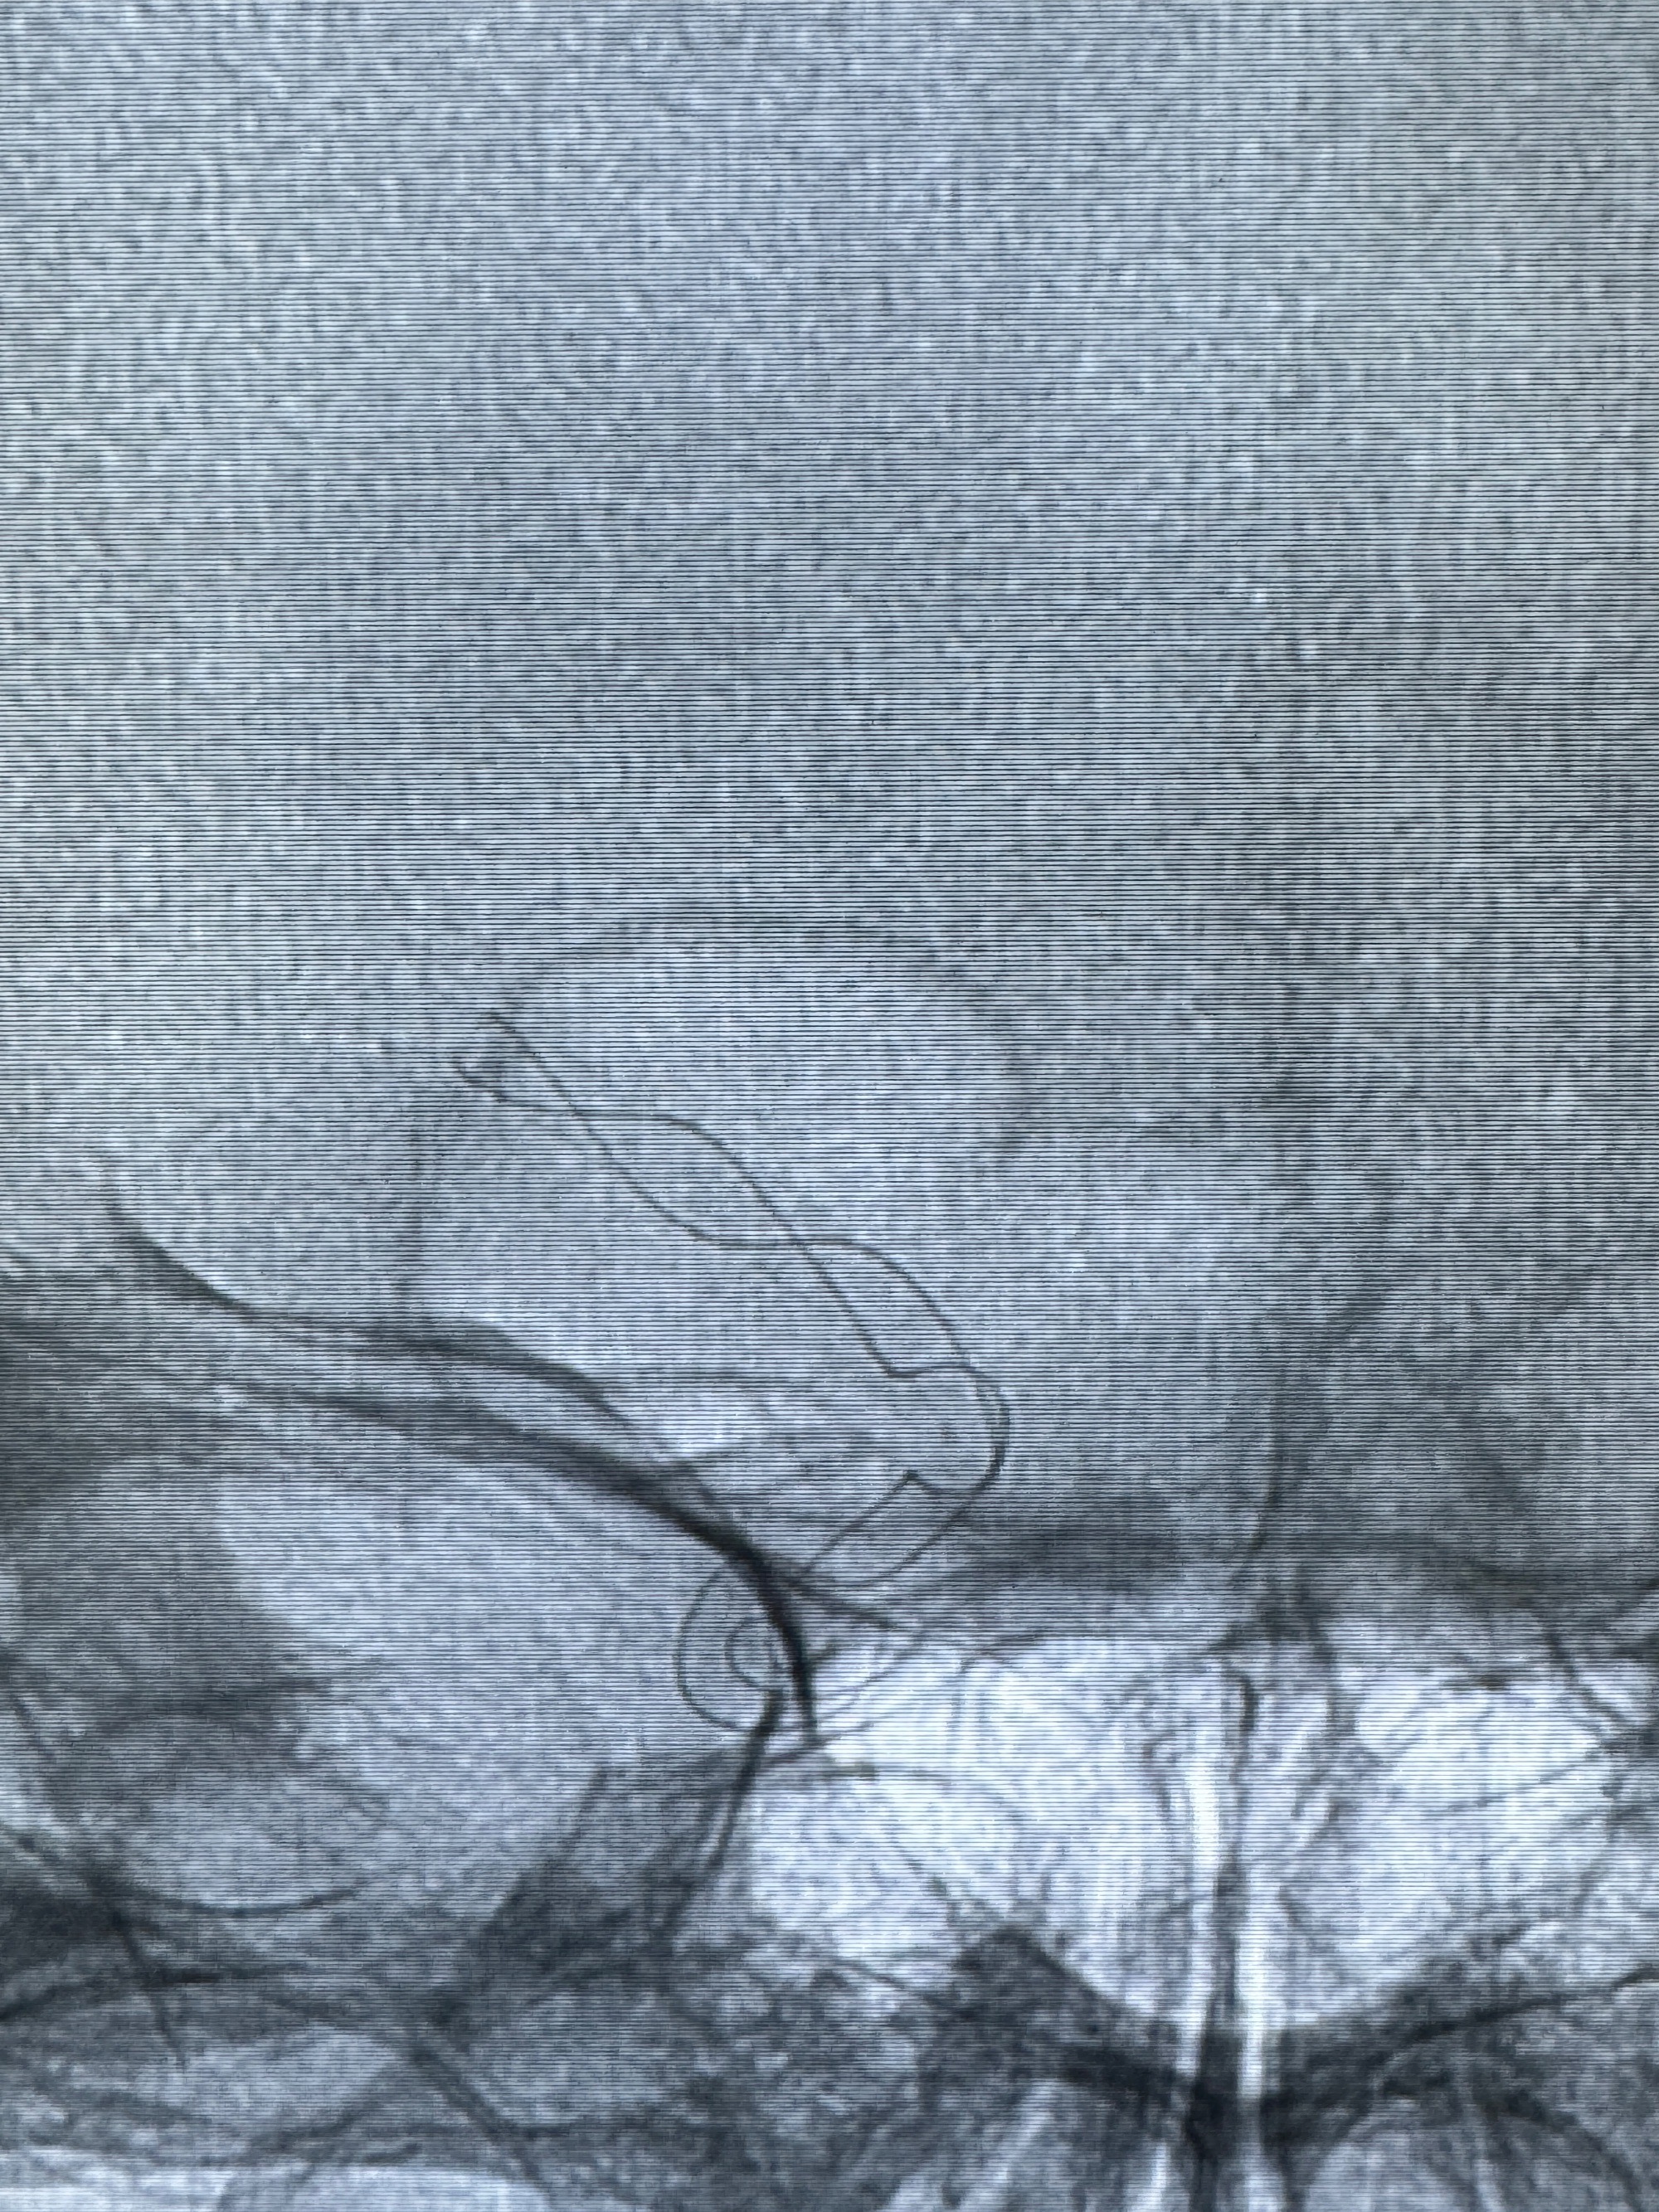

透视可见红圈部分为支架导管的头端

手推冒烟显示支架位置及展开情况,箭头为支架导管的位置

逐帧图像展示歪着脖子释放支架,旁边吩咐助手手机摄影、拍照留像(透视机不能留影像)

接下的视频为释放支架的过程及试图确认支架与血管的关系